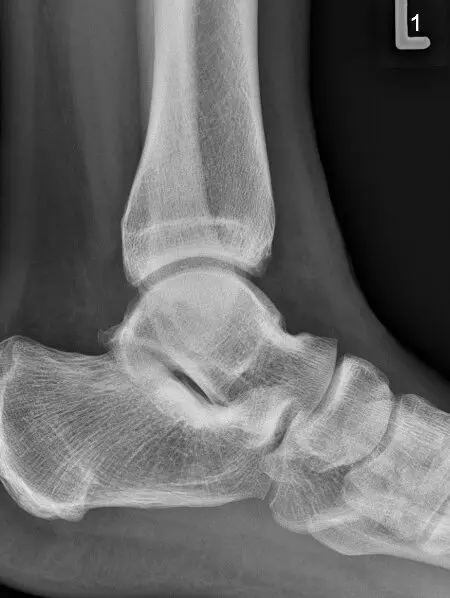

Obraz RTG stawu skokowego z zaawansowanymi zmianami zwyrodnieniowymi, w wyniku przebytego urazu – widok z boku